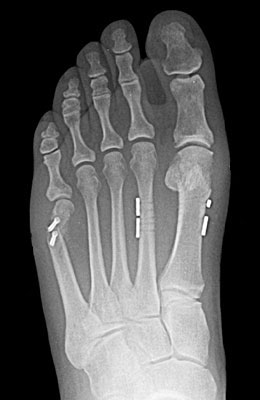

Before

Minimally Invasive Bunion Surgery before

After

Minimally Invasive Bunion Surgery after

Minimally Invasive Bunion Surgery featuring the miniBunon™ System and Tailors Bunionectomy

Melissa is a 32-year-old businesswoman who could not be off her foot post-surgery, yet she had a severely painful bunion. We performed our miniBunon™ System (our trademarked minimally invasive bunion surgery) and had a dramatic correction with no downtime. Melissa continued to work after her bunion surgery and was back in shoes and full activity at 5 weeks. Melissa could not believe the results of her Bunionectomy resulting in no bony bump, no scar and amazing motion. “After” picture taken immediately following surgery. Note the bunion and bunionette (Tailor’s bunion) in the before picture.